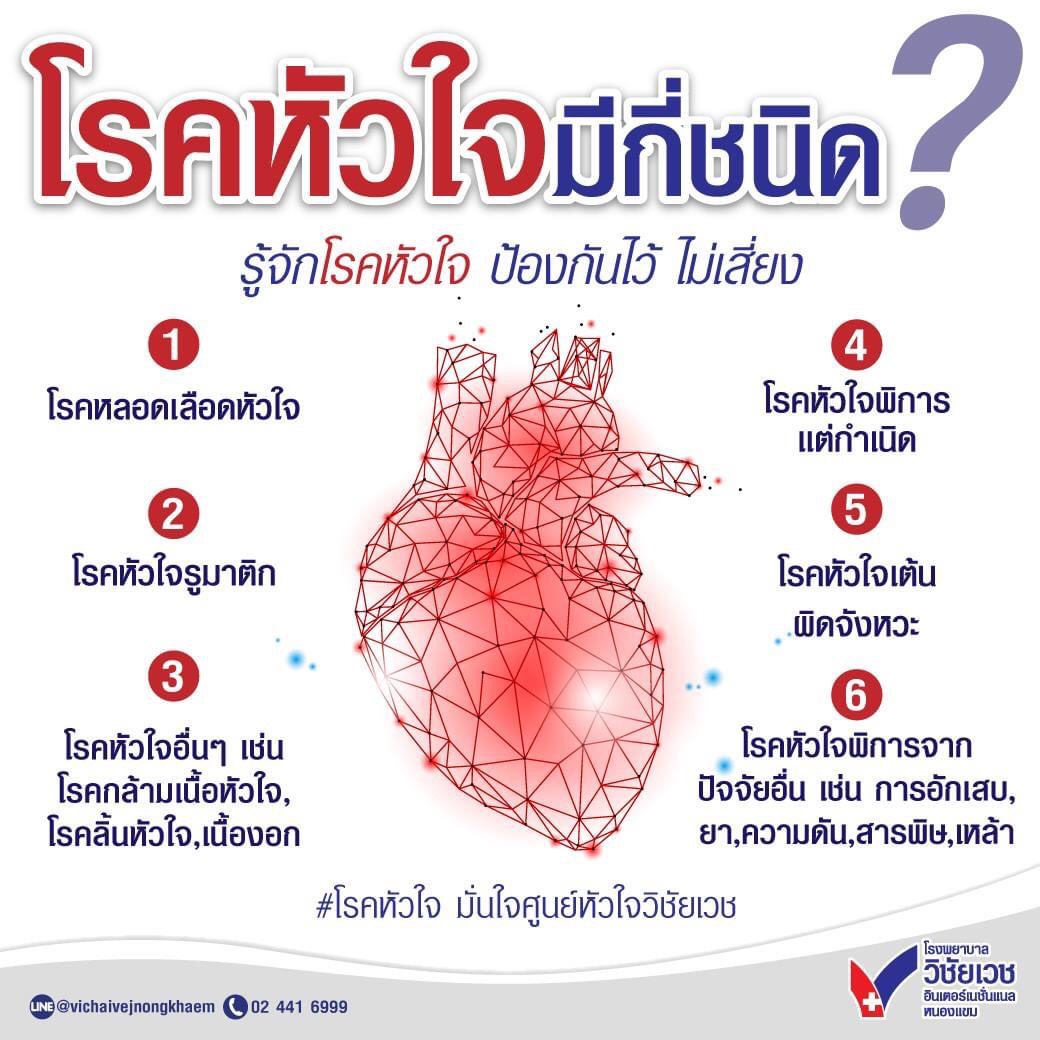

ช็อกโกแลต รูปฟุตบอล เหรียญทอง หัวใจ บรรจุ 60 ชิ้น | Shopee Thailand โรคหัวใจ อาการ และปัจจัยเสี่ยง – โรงพยาบาลวิชัยเวช อินเตอร์เนชั่นแนล …

โรคหัวใจ อาการ และปัจจัยเสี่ยง – โรงพยาบาลวิชัยเวช อินเตอร์เนชั่นแนล … ช็อกโกแลตรูปหัวใจ ลายสตรอเบอร์รี่ น่ารัก มุ้งมิ้ง วันวาเลนไทน์ …

หัวใจมนุษย์ การออกแบบรายละเอียด ภาพประกอบสต็อก – ดาวน์โหลดรูปภาพตอนนี้ … สายด่วน Hot Line 083-990-8989 ปรึกษาปัญหาโรคหัวใจตลอด 24 ชั่วโมง

สายด่วน Hot Line 083-990-8989 ปรึกษาปัญหาโรคหัวใจตลอด 24 ชั่วโมง The Heart หัวใจมนุษย์ 心脏